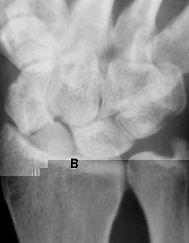

La mayoría de los restantes pacientes siguen acudiendo a revisiones periódicas, continuando hasta el presente con sus actividades laborales y/o deportivas, aunque cabe sospechar que un porcentaje indeterminado de los mismos va a necesitar en el futuro una intervención quirúrgica paliativa. Hemos comprobado que los mejores resultados se han obtenido con las prótesis sustitutivas de pequeños fragmentos (Fig. 2), y en mi experiencia las reintervenciones han sido precisas en prótesis parciales grandes, con frecuencia con estiloidectomía asociada, donde el desgaste y la inestabilidad del implante es mayor.

Figura 2. A: Pseudoartrosis del polo proximal. B: Prótesis parcial con vástago sustitutiva.